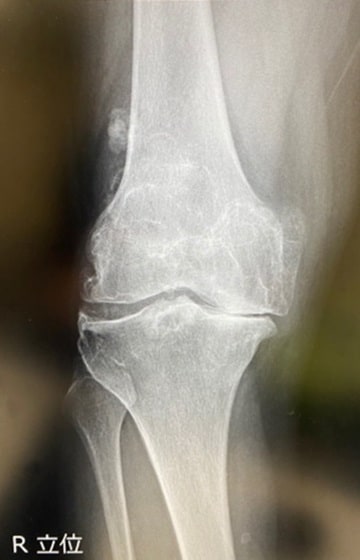

そんなとき、当院に来院されました。初診は2022年12月のこと。X線やCT、MRIなどの検査をしたところ、筋肉に損傷はなく、膝関節だけの問題であることが判明しました。

通常は画像診断のほか、膝の動きや可動域などを見て治療法を決定しますが、この患者さんの場合、変形が重度であるのに加えて、右膝を伸ばし切ることができず、マイナス20度くらいの状態で固まっていました。そのため、筆者は「末期の変形性膝関節症」と診断しました。根治するには人工膝関節置換術が最適であると伝えました。